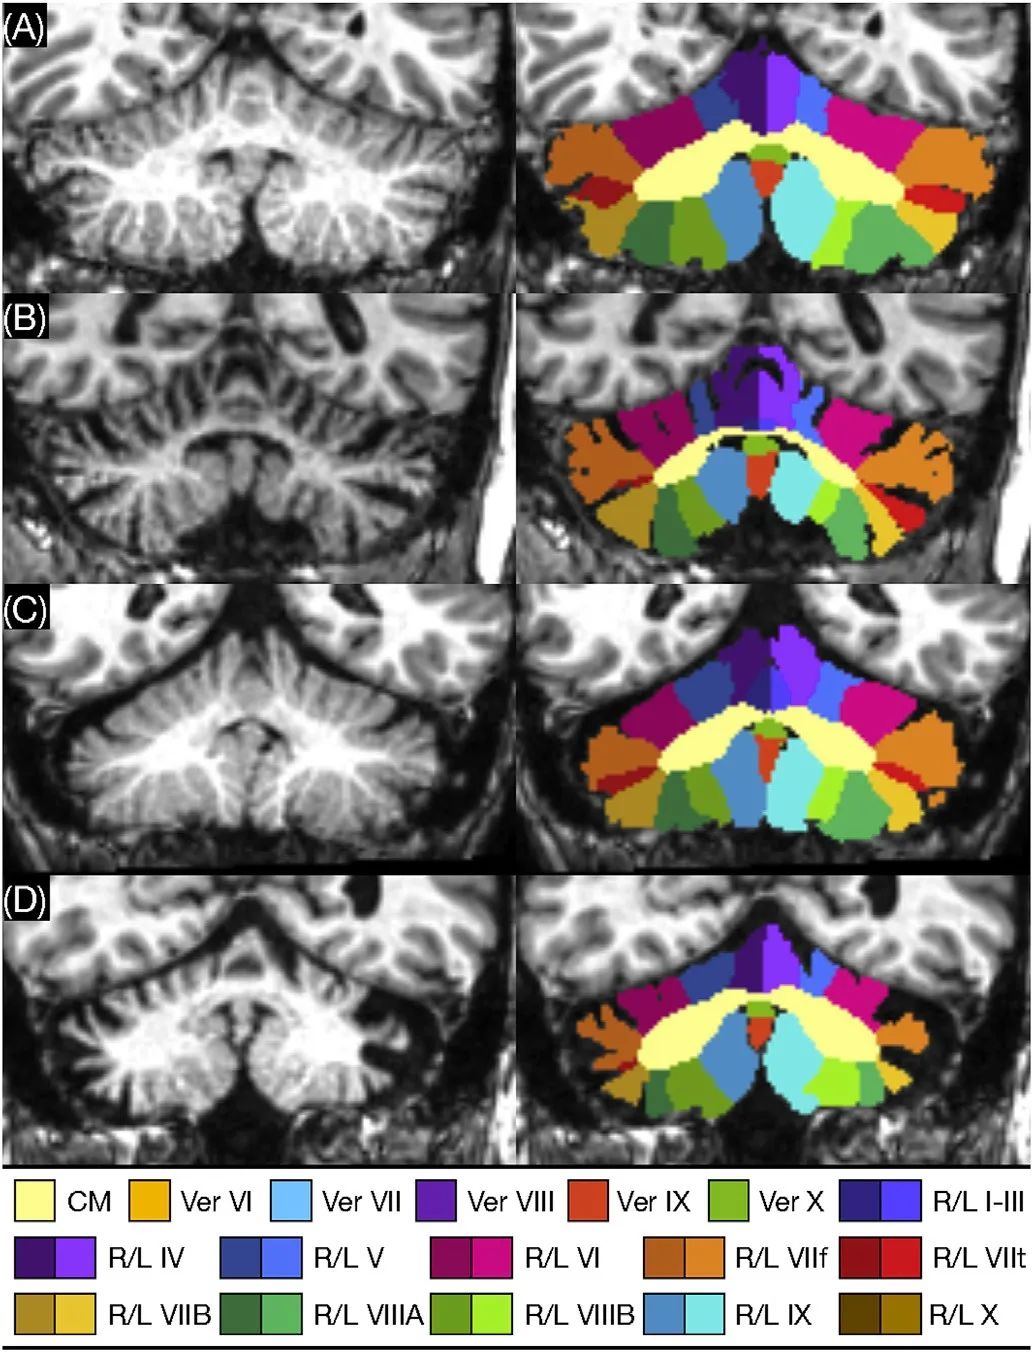

核磁影像数据在神经影像中占据大多数。近年来,深度学习已经在神经影像中得到了极大的普及。现在,许多神经影像任务(包括分割、配准和预测)都有基于深度学习的实现。此外,通过使用深度生成模型和对抗训练,深度学习为复杂图像合成任务的研究开辟了新途径。随着大型且多样化的影像数据集的诞生,神经影像学研究的可用性不断提高,这归咎于深度学习技术,不仅提高了准确性和通用性,同时减少了推理时间和降低了复杂预处理的需求。尤其是卷积神经网络 (CNN),实现了有效的网络参数化和空间不变性,并且降低了对特定领域知识的需求这在处理高维神经影像数据时至关重要,在一系列预测和分析任务中被证明有效。本综述面向神经图像分割和组织分类可变形的图像配准GAN在神经影像学中的应用这三方面展开了具体的调研。图4展示了通过级联深层网络方法获得的脑结构分割结果。

4)通过级联深层网络方法进行脑结构分割。来自于A)健康受试者;B)脊髓小脑共济失调(SCA)2型;C)SCA 3型;D)SCA 6型受试者。